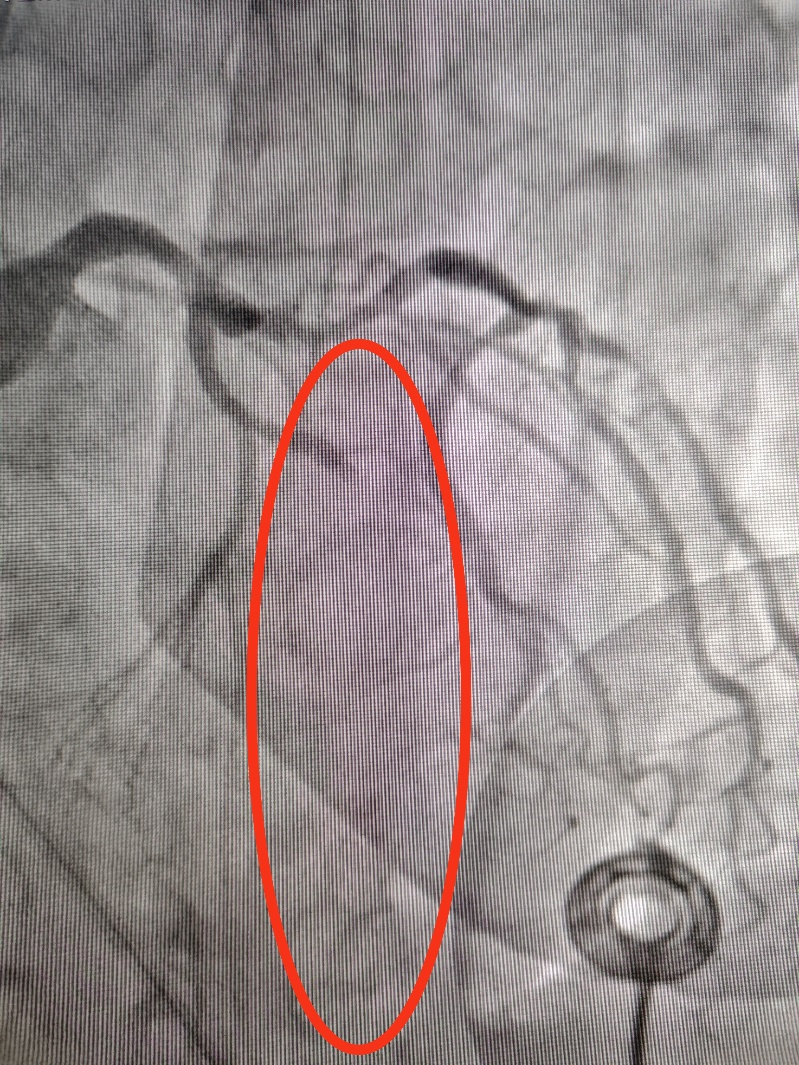

在心内、心外团队紧密协作下,一场与死神的赛跑紧张展开,40分钟完成床旁ECMO上机,20分钟完成床旁IABP植入,后续各种抢救药物不断调整,经过大约120分钟的全力奋战,患者生命体征逐步趋于平稳,为后续治疗赢得了宝贵时间。

为生命续航,从ECMO到PCI的闯关之路